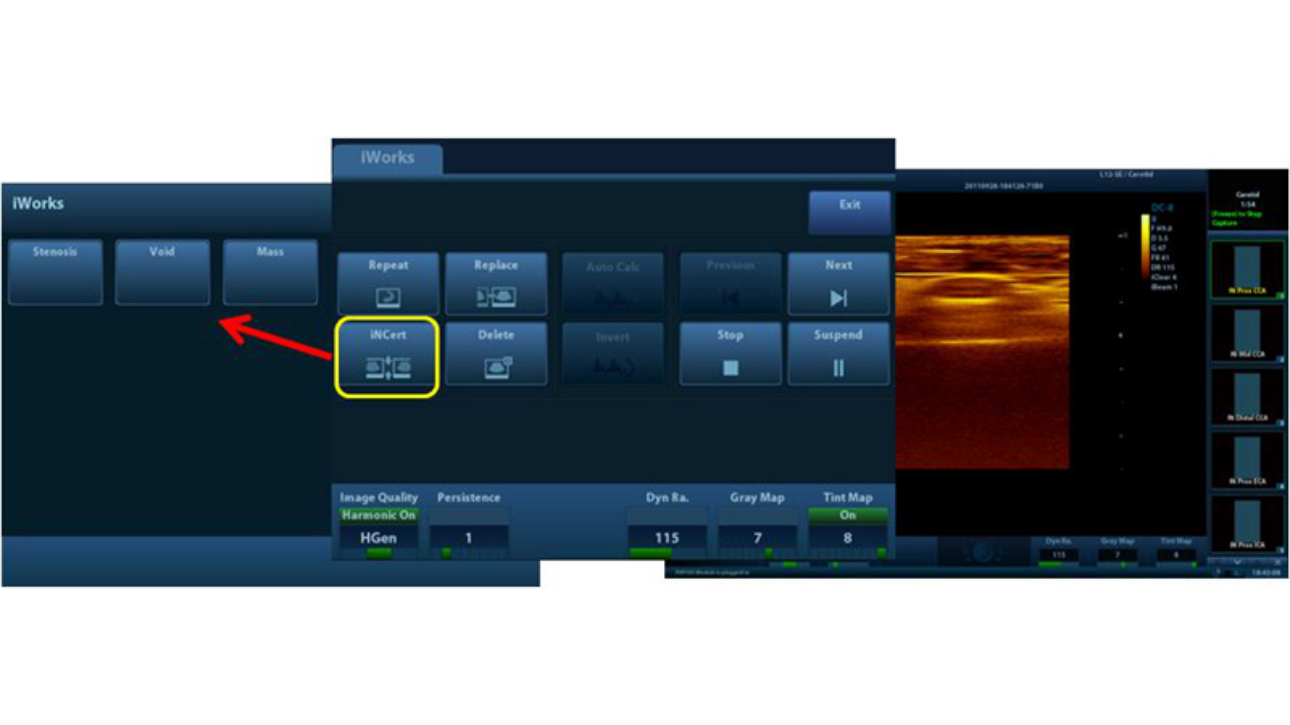

Auto IMT (Intima-Media Thickness)

Auto measurement of anterior and posterior wall thickness providing accurate carotid status.